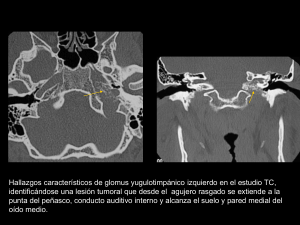

Fig. 6: Glomus yugulotimpánico izquierdo. TC, arteriografía